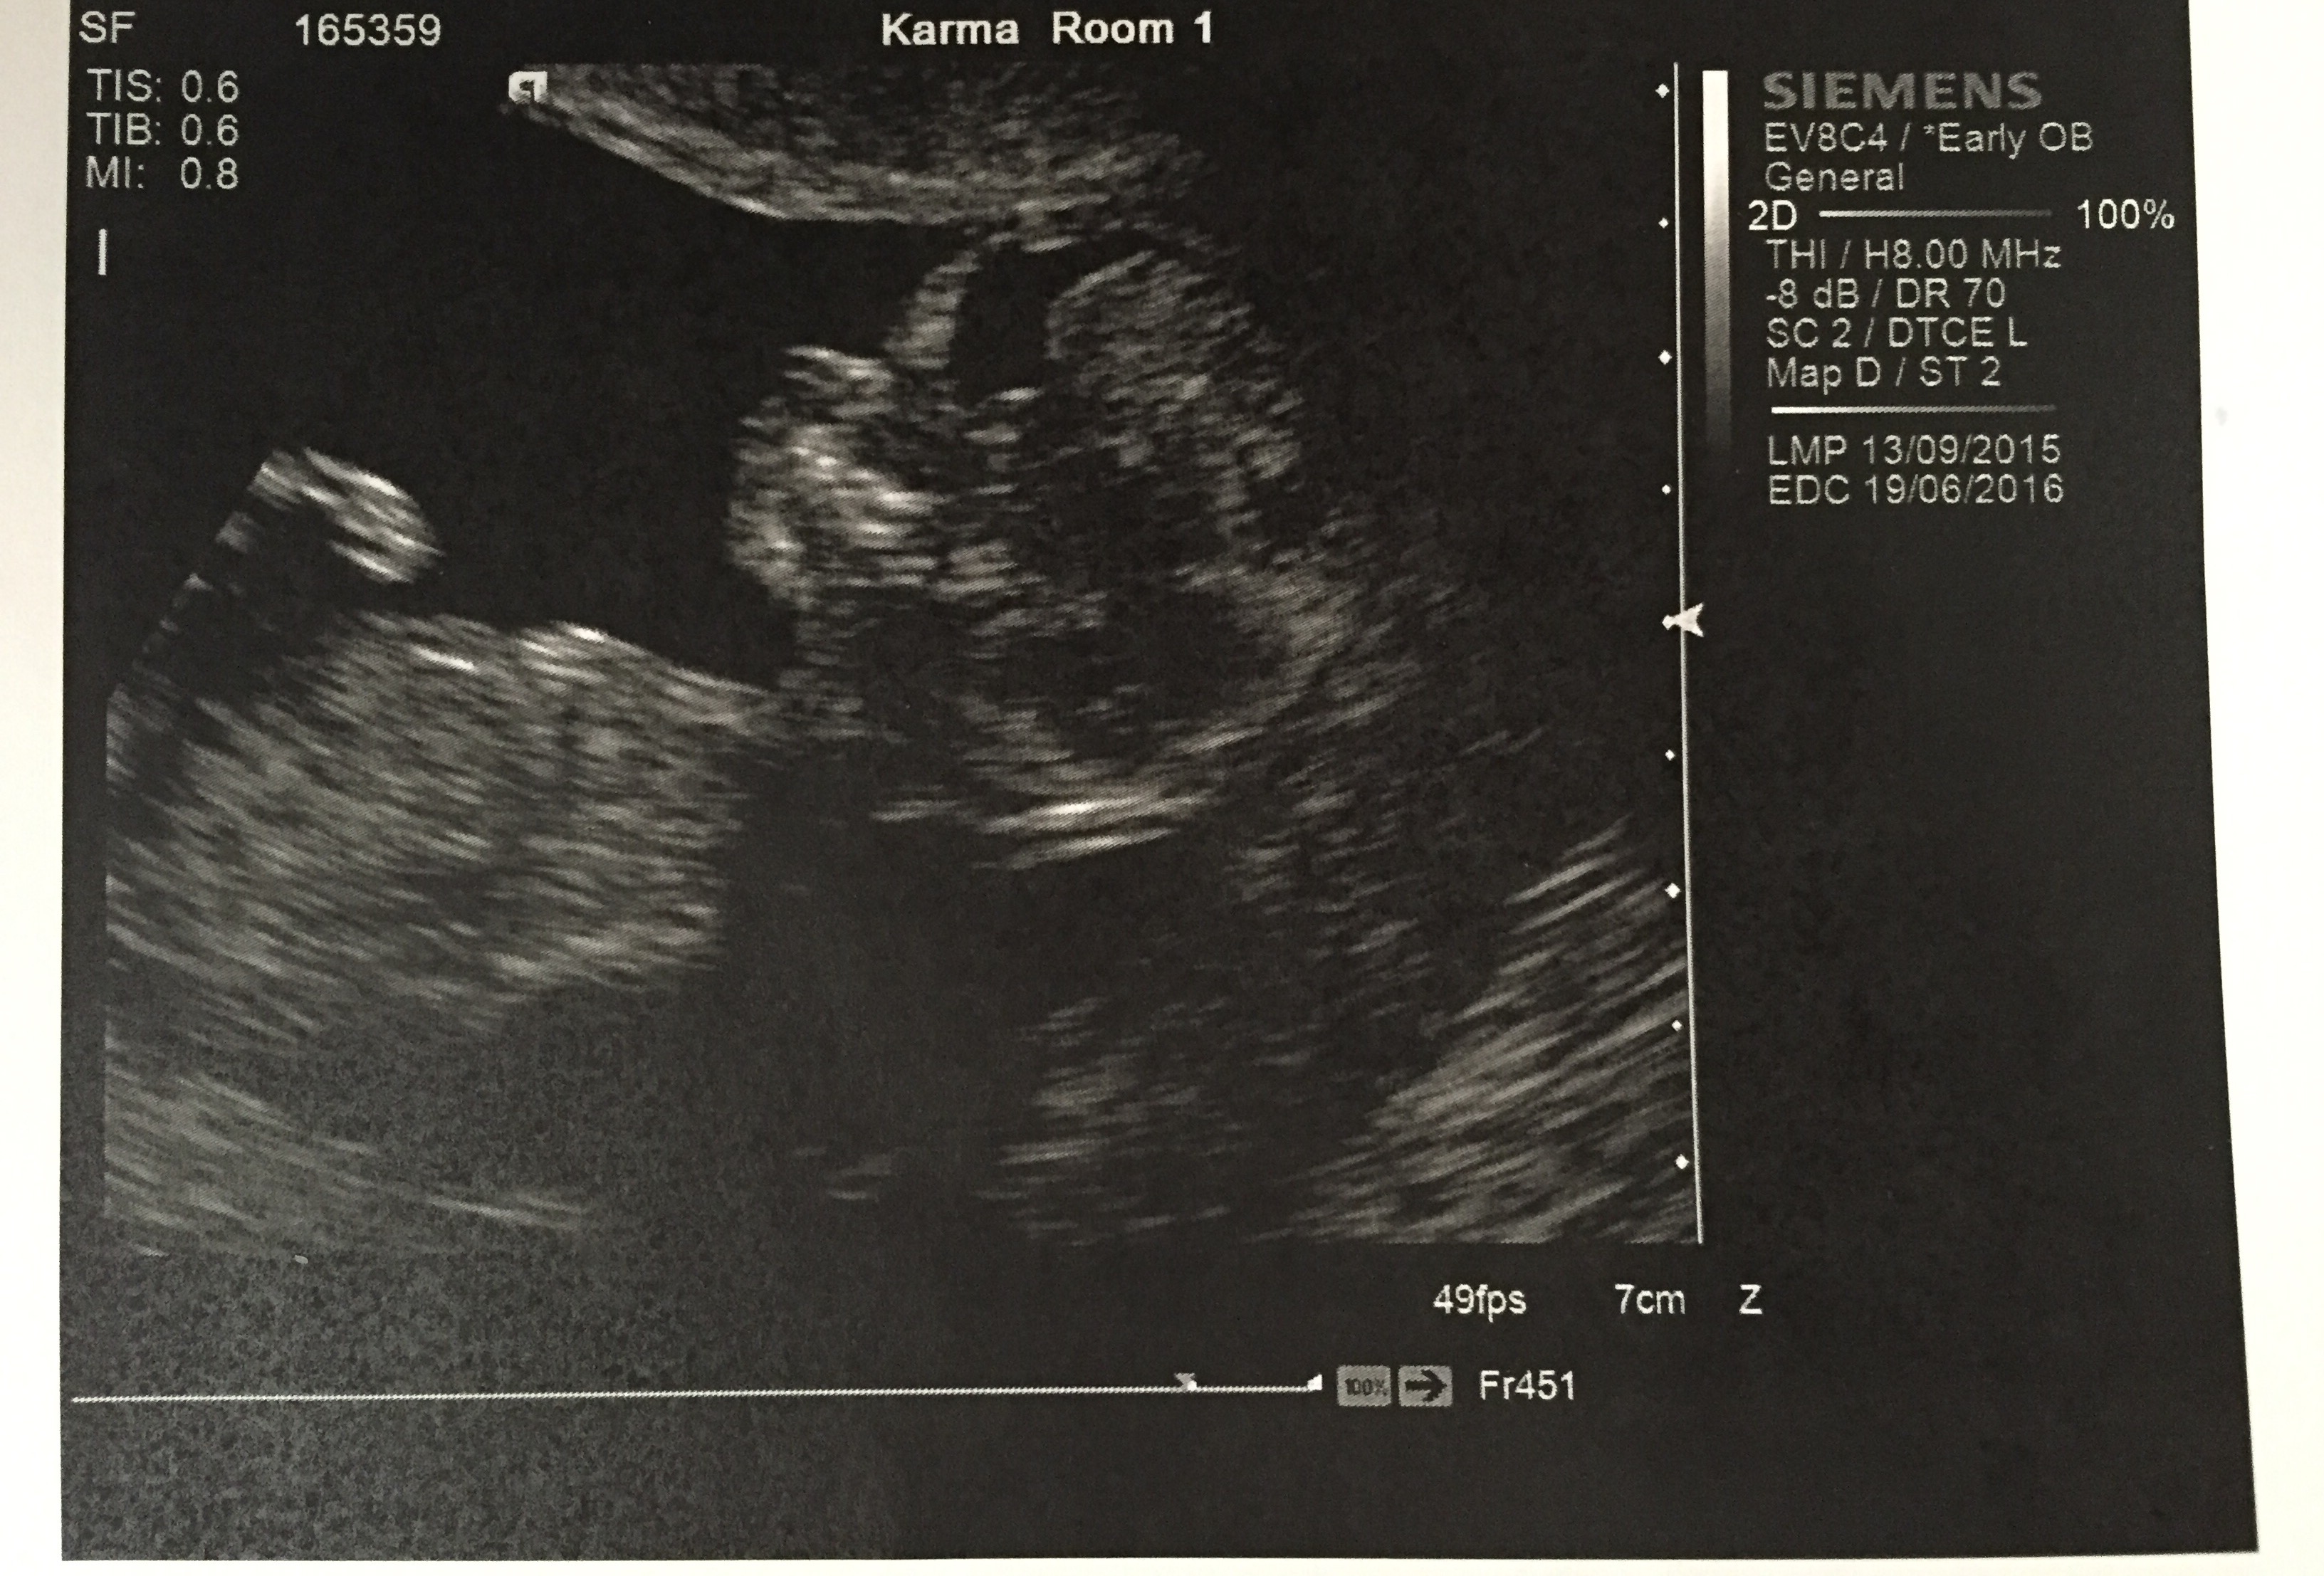

14 weeks 1 day. My Dr at my exam last week thought I felt further along, so we had this as a dating ultrasound and I was right. So happy I got to see baby!